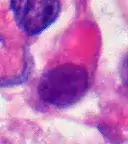

AT/RT Histology with numerous rhabdoid tumor cells Rhabdoid Tumor Cell - 400X Magnification

Rhabdoid Tumor Cell - 400X Magnification

The tumor histopathology is jumbled small and large cells. The tissue of this tumor contains many different types of cells including the rhabdoid cells, large spindled cells, epithelial and mesenchymal cells, and areas resembling primitive neuroectodermal tumor (PNET). As much as 70% of the tumor may be made up of PNET-like cells. Ultrastructure characteristic whorls of intermediate filaments are seen in the rhabdoid tumors (as with rhabdoid tumors in any area of the body). Ho and associates found sickle-shaped embracing cells, previously unreported, in all of 11 cases of AT/RT.[18]

Examination of the cerebrospinal fluid is important (CSF), as one-third of patients will have intracranial dissemination with involvement of the CSF. Large tumor cells, eccentricity of the nuclei, and prominent nucleoli are consistent findings.[23] Usually only a minority of AT/RT biopsies have rhabdoid cells, making diagnosis more difficult. Increasingly it is recommended that a genetic analysis be performed on the brain tumor, especially to find if a deletion in the INI1/hSNF5 gene is involved (appears to account for over 80% of the cases). The correct diagnosis of the tumor is critical to any protocol. Studies have shown that 8% to over 50% of AT/RT tumors are diagnosed incorrectly.